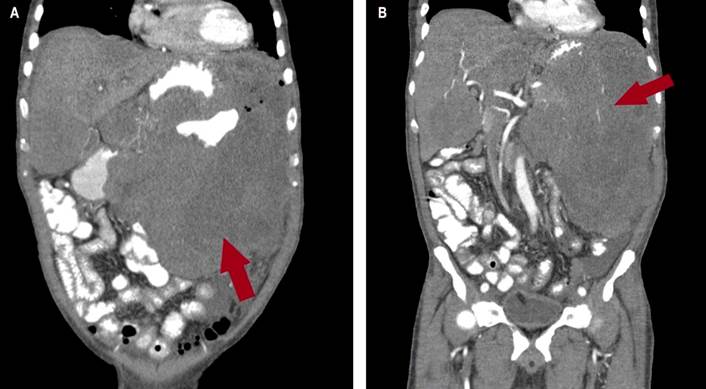

En la tomografía axial computarizada (TAC) de tórax se evidenciaba consolidación alveolar con infiltración en ambas bases pulmonares en vidrio deslustrado y engrosamiento septal (Figura 2). En la TAC de abdomen y pelvis se evidenció una masa tumoral de aspecto infiltrativo de aparente origen gástrico de aproximadamente de 25 x 25 x17 cm con extensa destrucción de la pared y la mucosa, con infiltración endoluminal y crecimiento extragástrico, metástasis hepática (hepatomegalia con dos lesiones hipoatenuantes de aspecto secundario, que miden 72 x 41 mm y 86 x 75 mm respectivamente en los segmentos hepáticos IV y V, e infiltración del hilio hepático, lo que produce dilatación de la vía biliar intrahepática) infiltración del bazo, del páncreas, de la raíz mesentérica, del omento mayor, del colon transverso, de las asas intestinales delgadas, de la porta y de los ganglios linfáticos periaórticos y pericavales, el mayor mide 13 mm (Figuras 3 y 4).